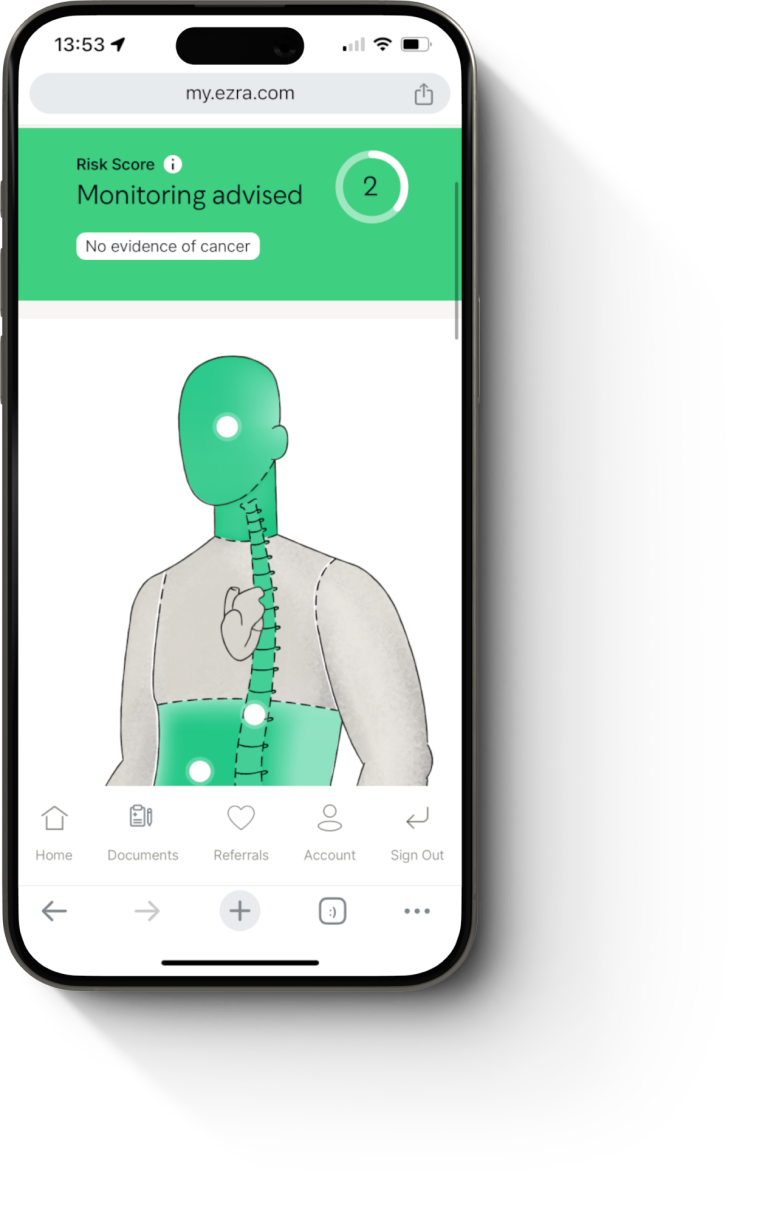

Ezra has 3 scan options designed to cater to your needs. Here are the differences:

MRI Scan: 500+ conditions including cancers of the brain, thyroid, liver, gallbladder, pancreas, spleen, kidneys, adrenal glands, bladder, ovaries, uterus, and prostate. Also scans for risk of strokes, risk of aneurysms, abnormal cysts, endometriosis, fatty liver, fibroids, kidney stones, hernias, iron overload, and diverticulitis.

MRI Scan with Spine: Everything in the MRI Scan, plus spine-specific coverage to detect herniated discs, cervical spinal stenosis, myelomalacia, spondylosis, spinal lesions, fractures, scoliosis, avascular necrosis, multiple myeloma, arthritis, and degenerative changes.

MRI Scan with Skeletal and Neurological Assessment: Everything in the MRI Scan with Spine. Also includes: scans for signs of neurodegeneration, multiple sclerosis and dementia; adds brain age analysis and body composition assessment (fat and muscle volume); hip evaluation for labrum, cartilage, and joint health; knee evaluation for meniscus, ACL, and MCL injuries.

Some locations may offer only the MRI Scan. Scan options can be confirmed in the MyEzra portal.